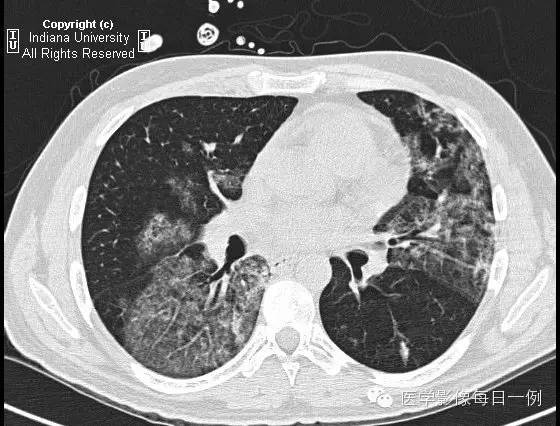

CT检查

【答案】2.D注释:支气管肺泡灌洗示肺出血,无合并性感染。

胸部CT示弥漫性肺泡透光度减低,主要位于右肺下叶和左肺上叶,呈铺路石样改变。胸膜无渗出。